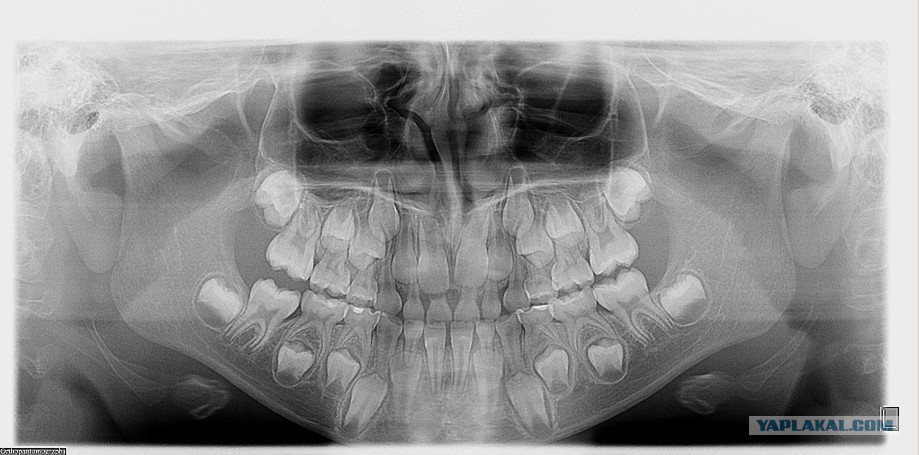

Удаление сверхкомплектного зуба